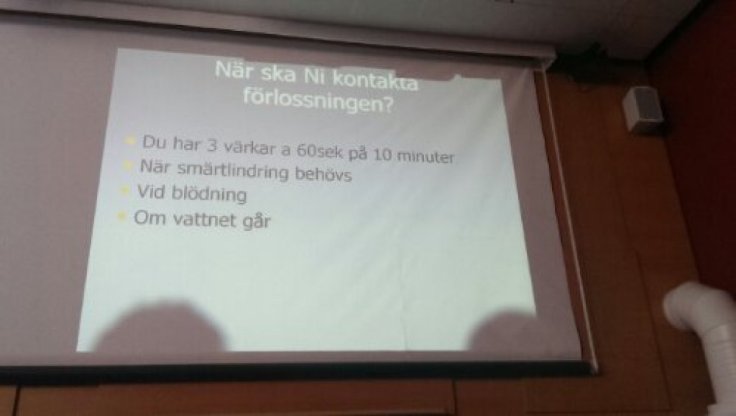

Om har man gått i 29 fulla veckor utan några bekymmer så får man väl stå ut med en och annan kullerbytta som dyker upp och nu kom en. I tisdags kväll när vi hade varit på Idas födelsedagskalas och haft en väldigt mysig kväll så upptäckte jag att jag blödigt lite och när jag sedan gjorde det på morgonen igen så ringde jag Danderyd för råd och dom sa att dom ville att jag skulle komma in för kontroll.

Efter ett dygn hemifrån så är det underbart att vara hemma igen, men nu har jag i alla fall rekognoserat vart vi ska vara då det är dags för nedsläpp.